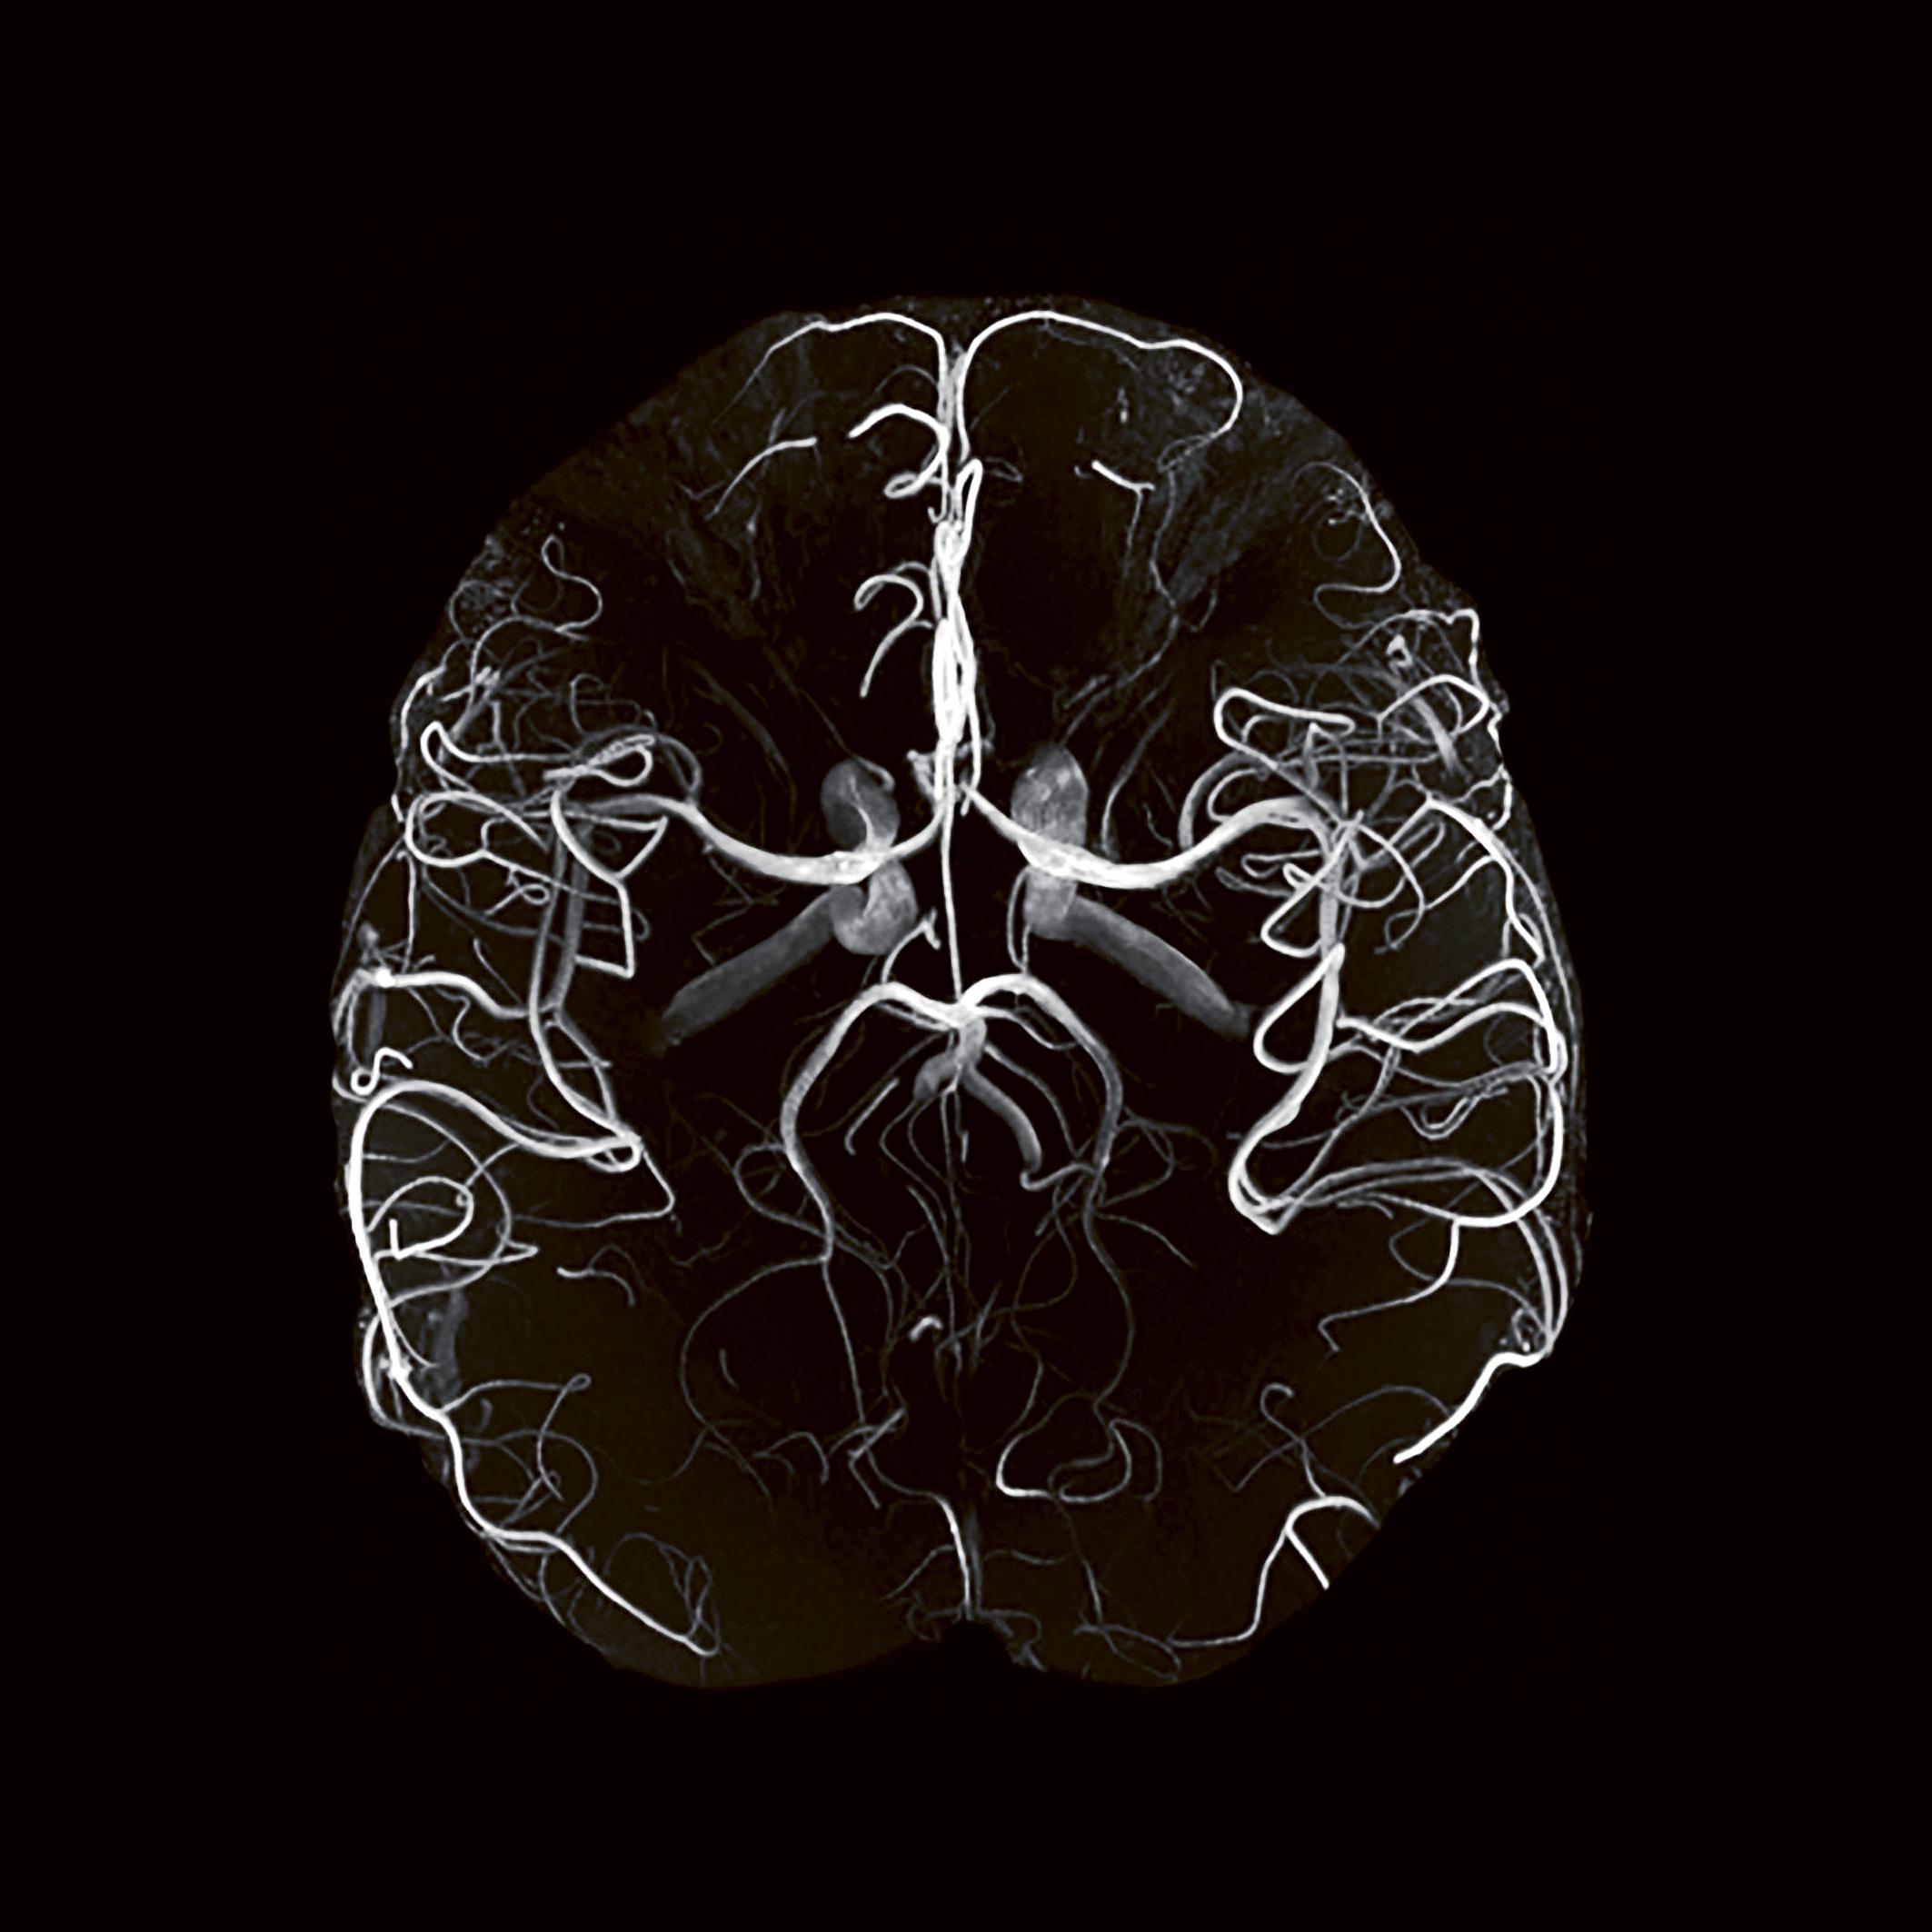

Angio-IRM montrant à haute résolution la vascularisation cérébrale.